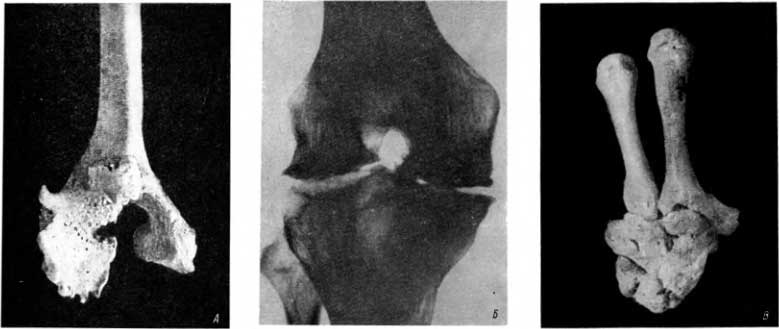

На многих трубчатых костях некоторые их участки являются уплощенными. В этих случаях может возникнуть вклинение наконечника стрелы в кость. И все же иногда это лишь поверхностное повреждение кости. Так, например, в погребении в Саркеле был найден скелет мужчины около 35 лет. Он был ранен стрелой, пущенной сзади. В правой бедренной кости, на границе средней и нижней трети диафиза, на задней уплощенной поверхности можно было отчетливо обнаружить костный выступ (рис. 14, А). Сходное образование описали Бегуан и Валлуа.[64] На рентгенограмме нами было обнаружено, что костный выступ представляет небольшую костную мозоль, возникшую в результате ранения конечности стрелой с металлическим наконечником. Металлический осколок как бы замурован в костной мозоли (рис. 14, Б). Стрела пробила в соответствующем участке ноги мощные слои мышц, потеряв свою кинетическую энергию; вклиниться глубоко в кортикальный слой кости и тем более в костномозговое пространство стрела уже не могла.

Рис. 14. A — костная мозоль на небольшом участке задней поверхности бедренной кости; Б — мелкий осколок металлического наконечника стрелы, покрытый тонким слоем костной мозоли; В — старый перелом ключицы в результате ранения острым колющим оружием, внизу — здоровая ключица того же человека.

Среди костей из погребения в Саркеле наше внимание привлекла несколько укороченная и деформированная ключица. В средней трети ее имеется клиновидно суживающийся дефект со сглаженными контурами (рис. 14, В) — это последствие ранения ключицы острым колющим оружием. Ранение вызвало перелом кости. Кость срослась. Гладкость контуров клиновидного дефекта также свидетельствует о давности ранения. Краевые костные разрастания на грудинном и акромиальном суставных концах ключицы говорят о преждевременной изнашиваемости соответствующих суставов.

При раскопках в том же городище был обнаружен скелет женщины (возраст около 45 лет). В средней трети диафиза правой локтевой кости имелся перелом с исходом в ложный сустав (рис. 15, А и Б). Наступающие в этих случаях изменения на мацерированных костях редко описывались. В этом новообразованном суставе дистальный отломок кости играл роль головки; возникшая в области повреждения замыкающая пластинка была очень тонкой (как в нормальных головках). Поврежденная же поверхность проксимального отломка служила суставной впадиной. Возникшая на ней замыкающая пластинка была склерозированной (как в нормальных суставных впадинах). Необычные условия движения и нагрузка привели к преждевременному деформирующему артрозу в локтевом суставе. Кости правого предплечья в общем тоньше (атрофичнее) костей левого предплечья.

Рис. 15. А — ложный сустав в локтевой кости, возникший после перелома Б — рентгенограмма локтевой кости с ложным суставом и нормальной лучевой кости.